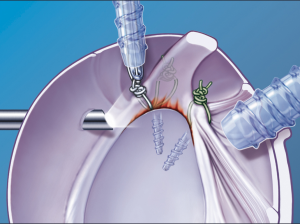

Ziel der operativen Behandlung ist die Wiedererlangung der Kraft und Beweglichkeit sowie die Schmerzausschaltung. Das operative Vorgehen richtet sich nach der individuellen Situation. Je nach Lokalisation, Ausmaß und Alter des Risses wird eine Naht bzw. Refixation der Sehne am Oberarmknochen in arthroskopischer (Abb. 3-8), immer seltener in offener Technik angestrebt.

Kann der Riss nicht arthroskopisch genäht werden, muss auf ein offenes Verfahren ausgewichen werden, wobei die refixierbaren Risse in der Regel gut arthroskopisch rekonstruiert werden.

Zusätzlich wird der Raum unter dem Schulterdach erweitert (Akromioplastik) (Abb. 9), da ansonsten die Nahtstelle unter dem Schulterdach aufgerieben wird.

- Arthroskopisch: Zeigt sich bei den Voruntersuchungen (Kernspin) und bei der Spiegelung ein abgelöstes Labrum (Gelenklippe) ohne wesentliche Kapselverletzung, so ist eine Refixierung des Labrums an den Pfannenrand mittels Knochenankern möglich. Zunächst wird eine diagnostische Arthroskopie (Gelenkspiegelung) zur Beurteilung des Verletzungsausmaßes des Pfannenrandes und der Kapselbandstrukturen sowie zur Beurteilung zusätzlicher Schäden durchgeführt. Anschließend erfolgt die arthroskopische Stabilisierung. Hierbei wird die abgelöste Gelenklippe (Labrum) mit dem Kapselbandapparat in ihrer ursprünglichen Position fixiert (Abb. 27 – 30).